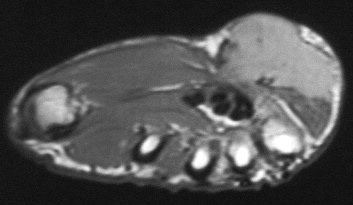

The preop MRI:

Click for larger image